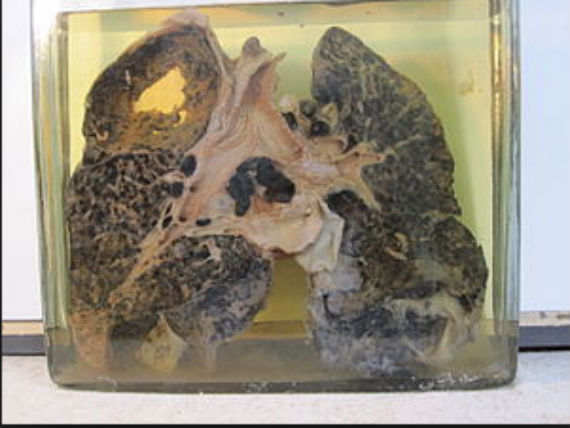

Las muertes y enfermedades que ocurren entre los trabajadores que limpian con chorros de arena o que perforan rocas son indicadoras de la gravedad de los riesgos de salud asociados con la exposición a la sílice. El hecho de respirar el polvo de sílice cristalina puede causar silicosis, que en sus aspectos más severos puede resultar en la discapacidad o la muerte. El polvo de sílice respirable entra en los pulmones y crea la formación de tejido de cicatriz reduciendo la capacidad de absorción de oxígeno por los pulmones. La silicosis no tiene cura. Dado que afecta el funcionamiento de los pulmones, uno es más susceptible de contraer infecciones pulmonares como la tuberculosis.